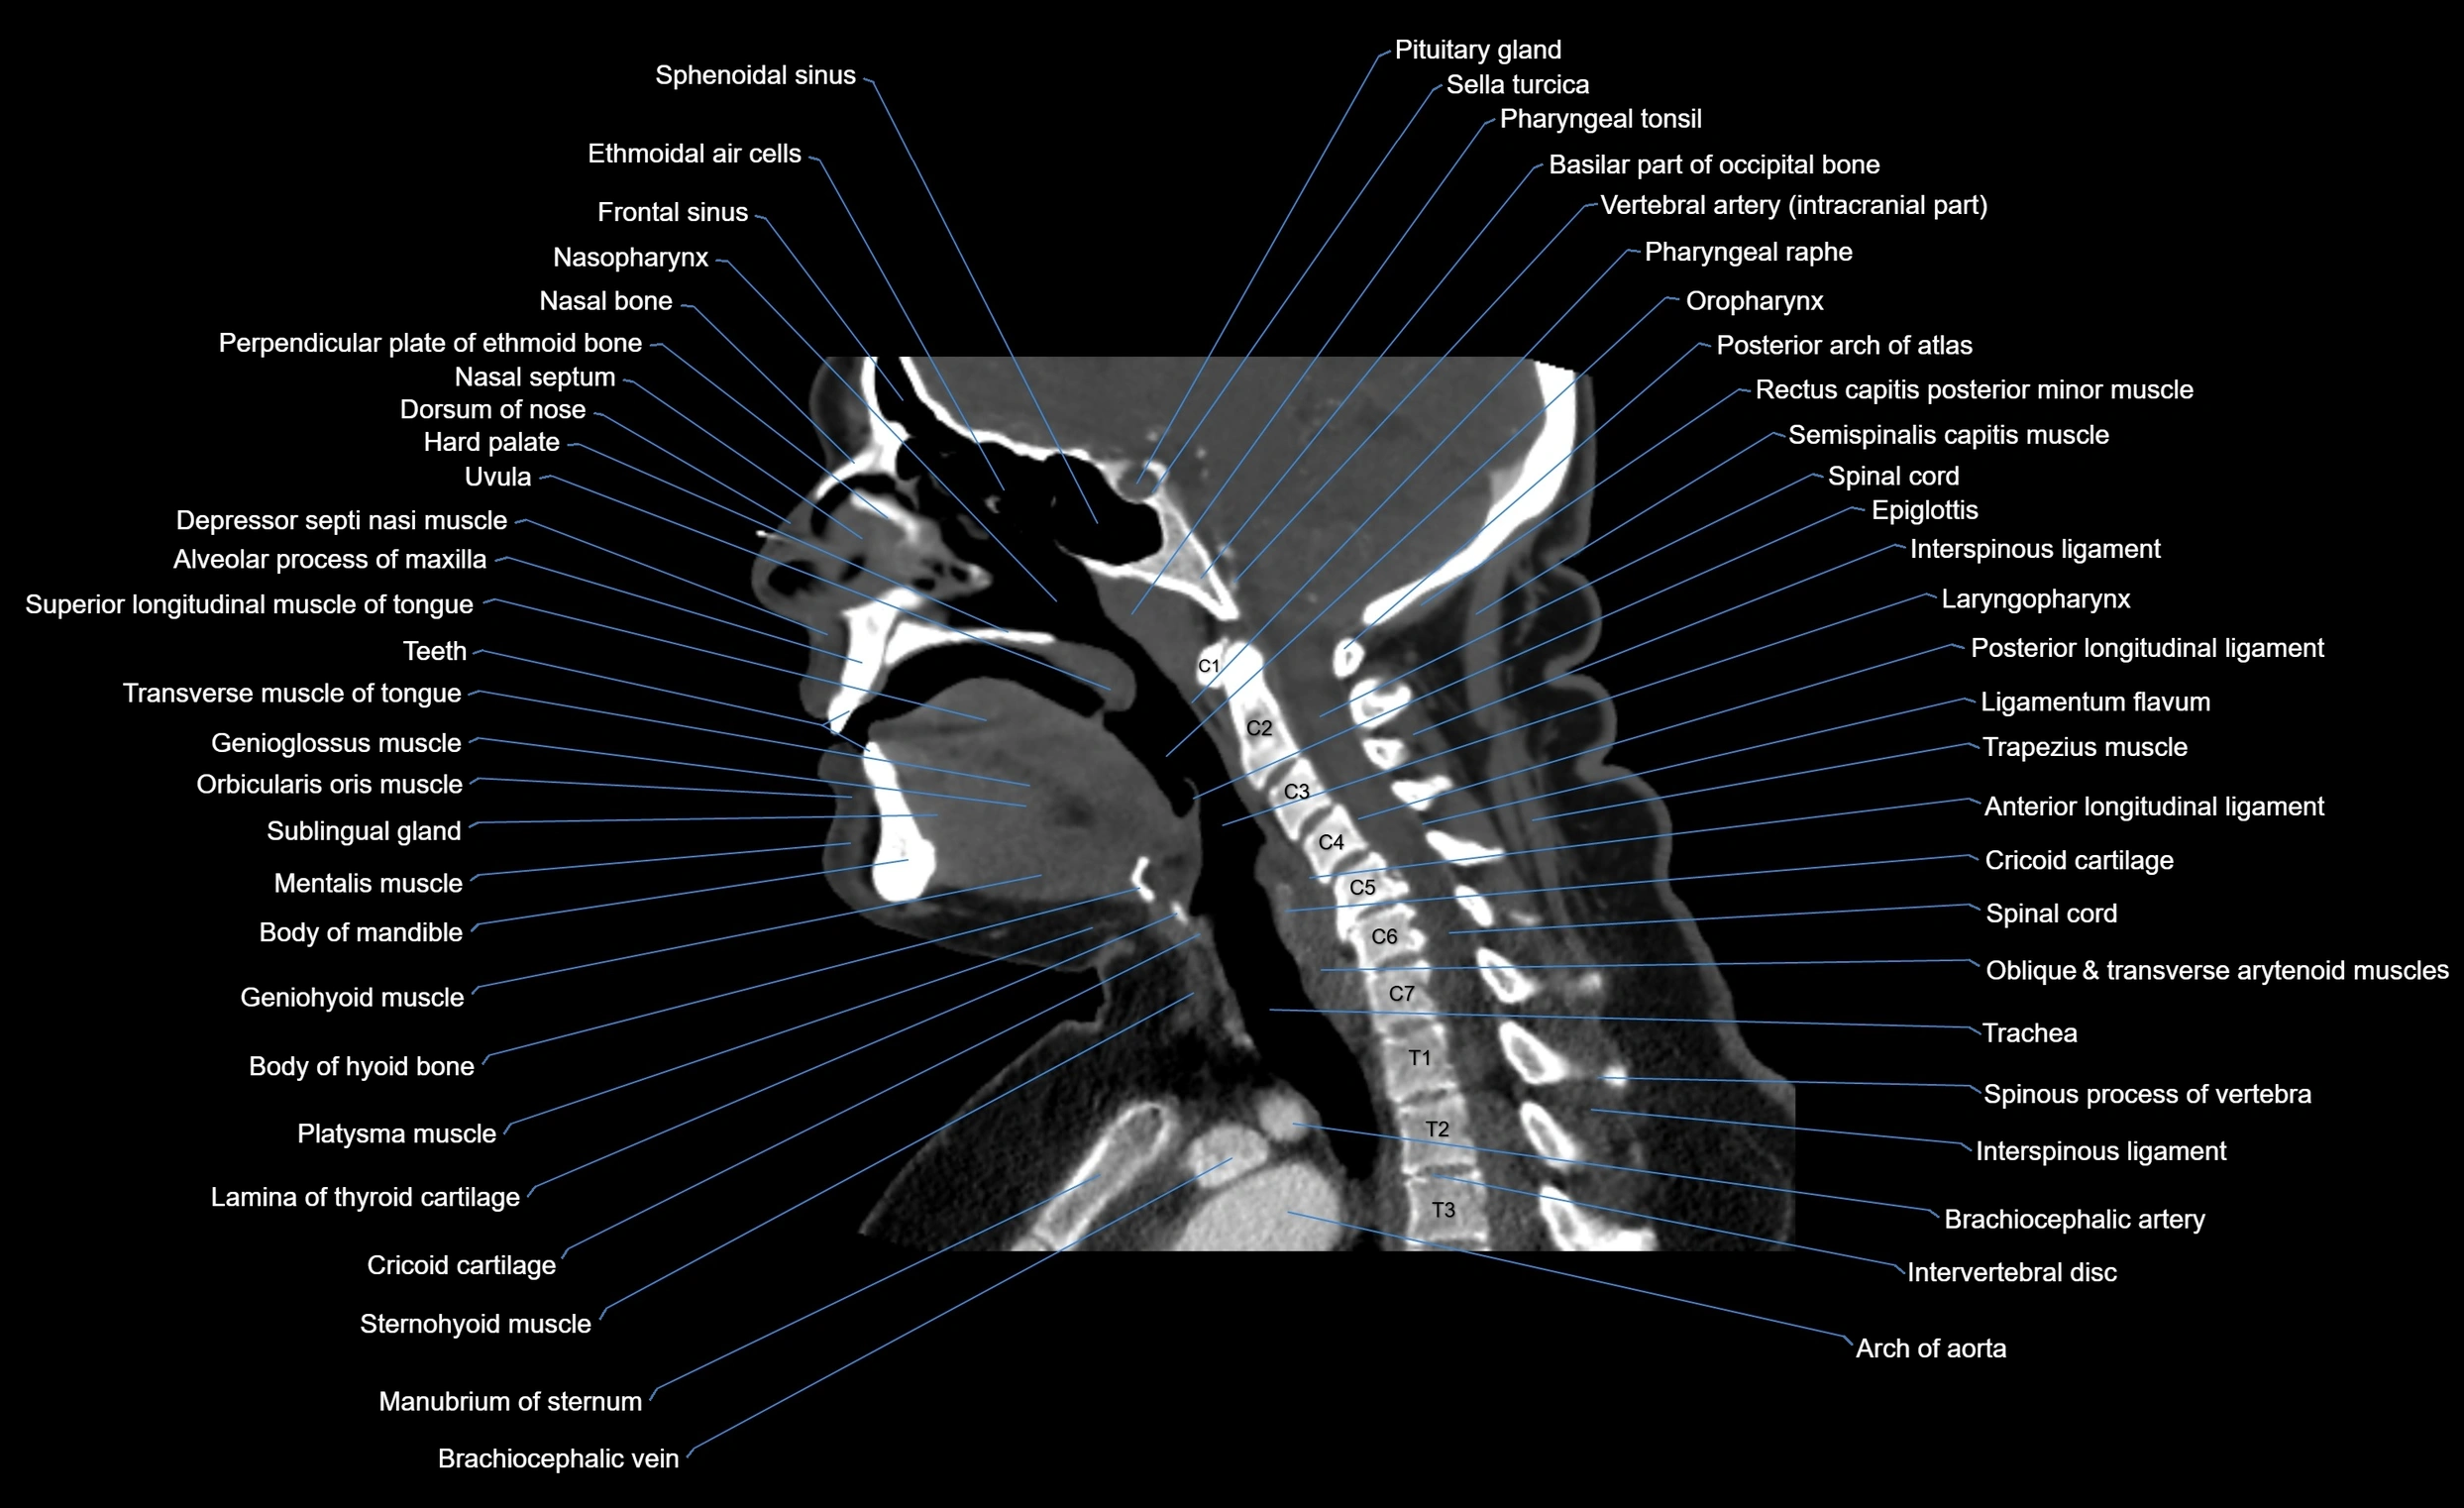

- Frontal sinus

- Ethmoidal air cells

- Nasopharynx

- Hard palate

- Spinal cord

- Epiglottis

- Cricoid cartilage

- Trachea

- Anterior longitudinal ligament

- Posterior longitudinal ligament

- Laryngopharynx

- Oropharynx